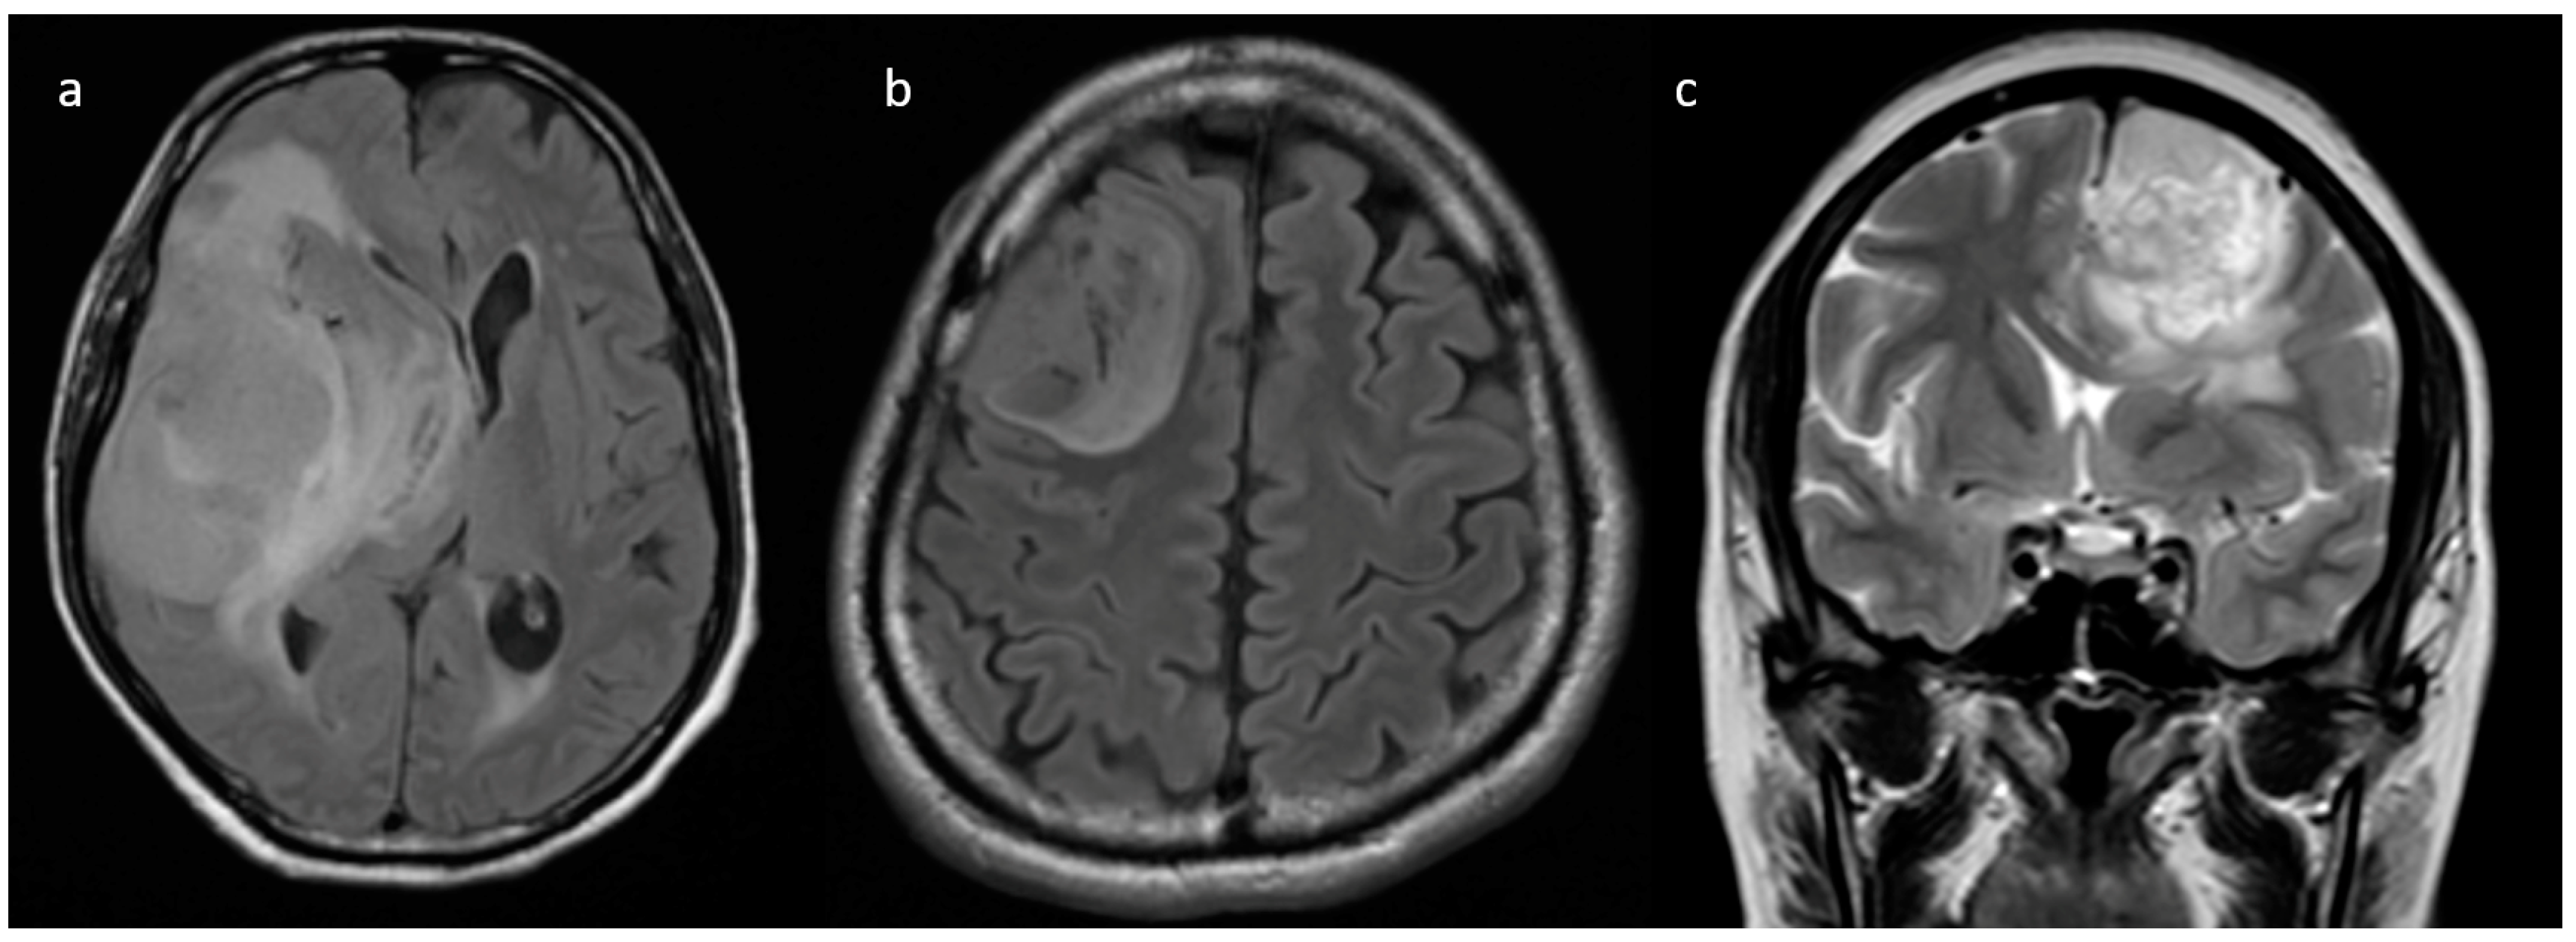

3.2. MRI Parameters of IDH-Wildtype vs. Mutant Phenotype Tumors